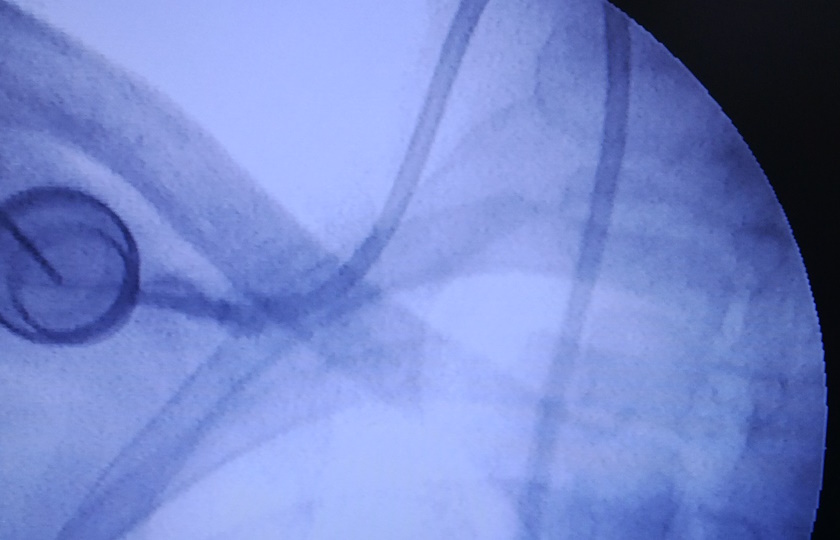

The neck vein is punctured under doppler guidance and a guide wire is passed till the heart. The catheter is passed over the wire and the position of the tip is checked under an X-ray or C-Arm. The other end of the catheter tunnelled beneath the collar bone and is connected to the portal, which is then implanted beneath the skin through a small incision.